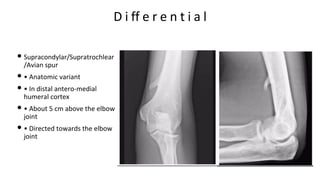

D i ff e r e n t i a l

• Supracondylar/Supratrochlear

/Avian spur

• • Anatomic variant

• • In distal antero-medial

humeral cortex

• • About 5 cm above the elbow

joint

• • Directed towards the elbow